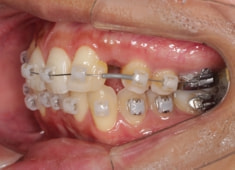

症例紹介

左上3番埋伏歯

治療法:フルパッシブブラケット:T21

治療開始時